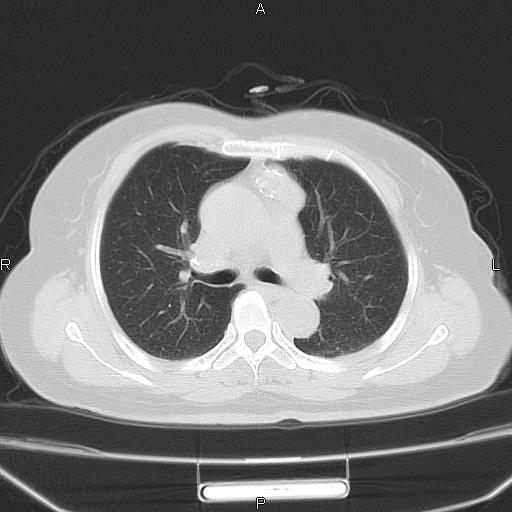

胸腺瘤

女、63Y 双眼睑下垂,早轻晚重。 胸腺瘤???

结果胸腺瘤